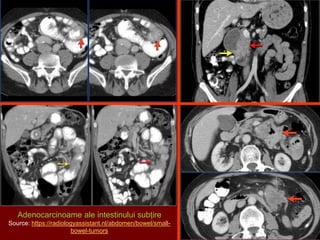

ADENOCARCINOAMELE

• cele mai frecvente (25-40% din neoplasmele intestinului subțire)

• tipuri histologice: adenocarcinoame mucinoase, nediferenţiate, diferenţiate

Semne imagistice:

a) Forma infiltrativă - zonă scurtă de îngustare a calibrului, rigidă, întreruperea pliurilor

mucoase, reacţia desmoplastică împiedică stenoza completă;

b) Forma vegetantă - lacună endoluminală unică sau multiplă, contur neregulat, semitonuri,

îngustare excntrică a lumenului, pliuri amputate, uneori ulceraţii.

Adenocarcinoame ale intestinului subțire

Source: https://radiologyassistant.nl/abdomen/bowel/small-

bowel-tumors